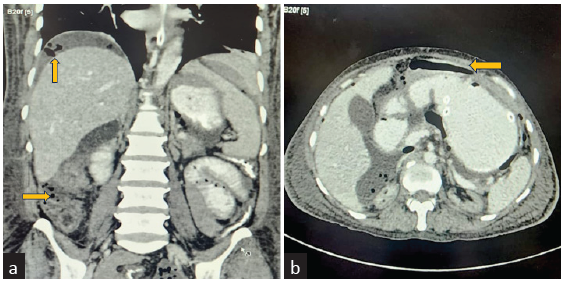

Dialysate total cell count showed no improvement after 3 days, and she developed abdominal distension and obstipation. Contrast-enhanced computed tomography (CECT) abdomen revealed colon perforation [Figure 1]. Laparotomy revealed perforation near the proximal two-third and distal one-third junctions of the transverse colon. Feculent peritoneal fluid was drained and end transverse colostomy was done. Despite intensive care, including mechanical ventilation, inotropic support, and continuous renal replacement therapy, she developed multiorgan failure and died on the tenth day.

- Contrast-enhanced computed tomography images (a) coronal view and (b) axial view showing multiple extra-luminal air attenuating foci in the non-dependant portion of the intra-peritoneal compartment of the abdomen (yellow arrows).